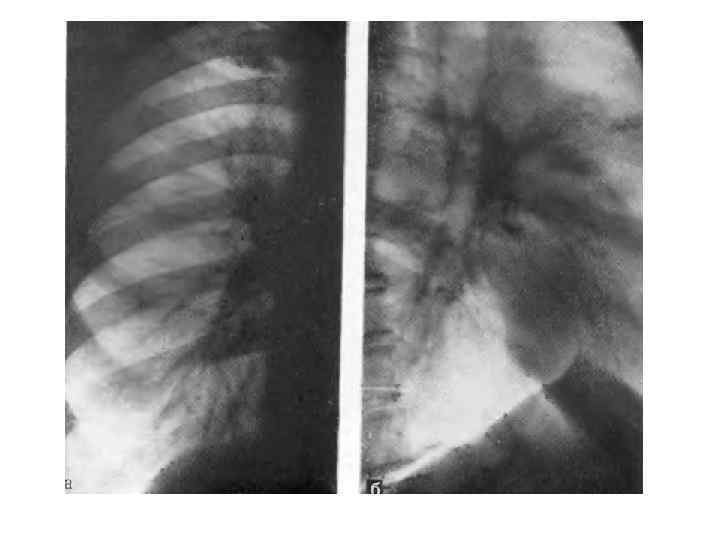

Ателектаз развивается при полной обтурации бронха опухолью, характеризуется полным рассасыванием воздуха из легочной ткани и резким ее объемным уменьшением. Кроме этих прямых признаков, как и при дистелектазе, большое диагностическое значение имеют вторичные симптомы, в той или иной степени сопутствующие ателектазу. Это, в первую очередь, смещение междолевой плевры и ее вогнутость в сторону объемного уменьшения. Выявляются также смещение корня легкого к ателектазу, средостения в сторону поражения, подъем купола диафрагмы и сужение межреберий на больной стороне, викарная эмфизема прилежащих участков легкого. Эти признаки также неспецифичны и указывают на объемное уменьшение легкого. В ателектазе также часто развиваются воспалительные и деструктивные изменения. Диагностировать их не всегда удается, лишь в отдельных случаях развиваются полости с газом и уровнями жидкости. Признаком тяжелой, обширной гнойной деструкции в ателектазе является нормальный размер доли или даже ее объемное увеличение такие случаи требуют неотложной хирургической помощи. При формировании ателектазов сегментов, долей соблюдаются определенные правила, знание которых облегчает топическую ориентировку и сокращает диагностический поиск. Во первых, любой ателектазированный участок смещается медиально и обязательно связан с корнем легкого. Во вторых, тень ателектаза смещается туда, где в норме располагались до этого сегмент или доля. В третьих, все доли и сегменты, граничащие с междолевой плеврой, в определенных проекциях обязательно сохраняют четкость очертаний. Участки же, не соприкасающиеся с плеврой, в любой проекции имеют размытый контур. Кроме медиального направления, доли спадаются следующим образом:

справа верхняя вверх и вперед, средняя вперед, нижняя вниз и кзади; слева верхняя вперед, нижняя вниз и кзади. Напомним сегменты, граничащие с междолевой плеврой: справа в верхней доле S 2 и S 3 , нижней S 6, S 7, S 8, слева в верхней S 1 2, S 4 и S 5, нижней S 6 и S 8. Оба сегмента средней доли ограничены междолевой плеврой. При формировании ателектазов междолевая плевра часто значительно изменяет свое положение и выявляется в проекциях, перпендикулярных тем, в которых она видна в норме. Например, при ателектазе средней доли горизонтальная междолевая плевра прослеживается только в боковой проекции, при ателектазе S 6 с обеих сторон (особенно часто слева) косая междолевая плевра отчетливо видна в прямой проекции. Сочетание ателектазированных долей и сегментов указывает на пораженный бронх, но не всегда эта зависимость соблюдается в полной мере. При резком стенозировании просвета бронха может не быть признаков нарушения вентиляции ткани легкого. И наоборот, при четко видимом просвете может сформироваться дистелектаз паренхимы. Такой вариант особенно характерен для рака Б 1 2 слева, часто имеющего перибронхиальный стелющийся рост и сопровождаемого симптомом "удлинения бронха".

Некоторые виды ателектазов носят "скрытый" характер и для их выявления требуется внимательность, опыт и соблюдение методик обследования. В первую очередь, это ателектаз нижней доли слева, который "прячется" ретрокардиально и проявляется в прямой проекции лишь дополнительным паракардиальным контуром. Не видна порой в прямой проекции ателектазированная средняя доля, зато не заметить ее на боковом снимке невозможно. Бывают случаи, когда на фоне ателектаза, дистелектаза или обтурационной пневмонии определяются просветы мелких бронхов на большом протяжении. Выявление такой воздушной бронхограммы может быть причиной роковой диагностической ошибки. Этот симптом считается патогномоничным для воспалительных процессов в легких, особенно популярен при КТ диагностике. Однако для воспалительных процессов неукоснительно соблюдается следующее правило воздушная бронхограмма должна быть прослежена на всем протяжении, от главного, долевого бронхов до мелких ветвей. Если есть участки прерывания просвета бронхов, то в первую очередь следует думать о центральном раке. Полный ателектаз доли, легкого часто не позволяет определить истинные размеры опухолевого узла в корне. В силу их одинаковой плотности даже КТ без контрастирования не поможет в таких случаях, и лишь КТ с болюсным усилением иногда может дать возможность дифференцировать ателектаз от опухоли. На фоне ателектаза не следует пытаться искать очертания опухоли или лимфоузлов, так как истинные контуры в легких формируются не границе двух тканей воздушной и безвоздушной (то есть мягкотканной плотности).